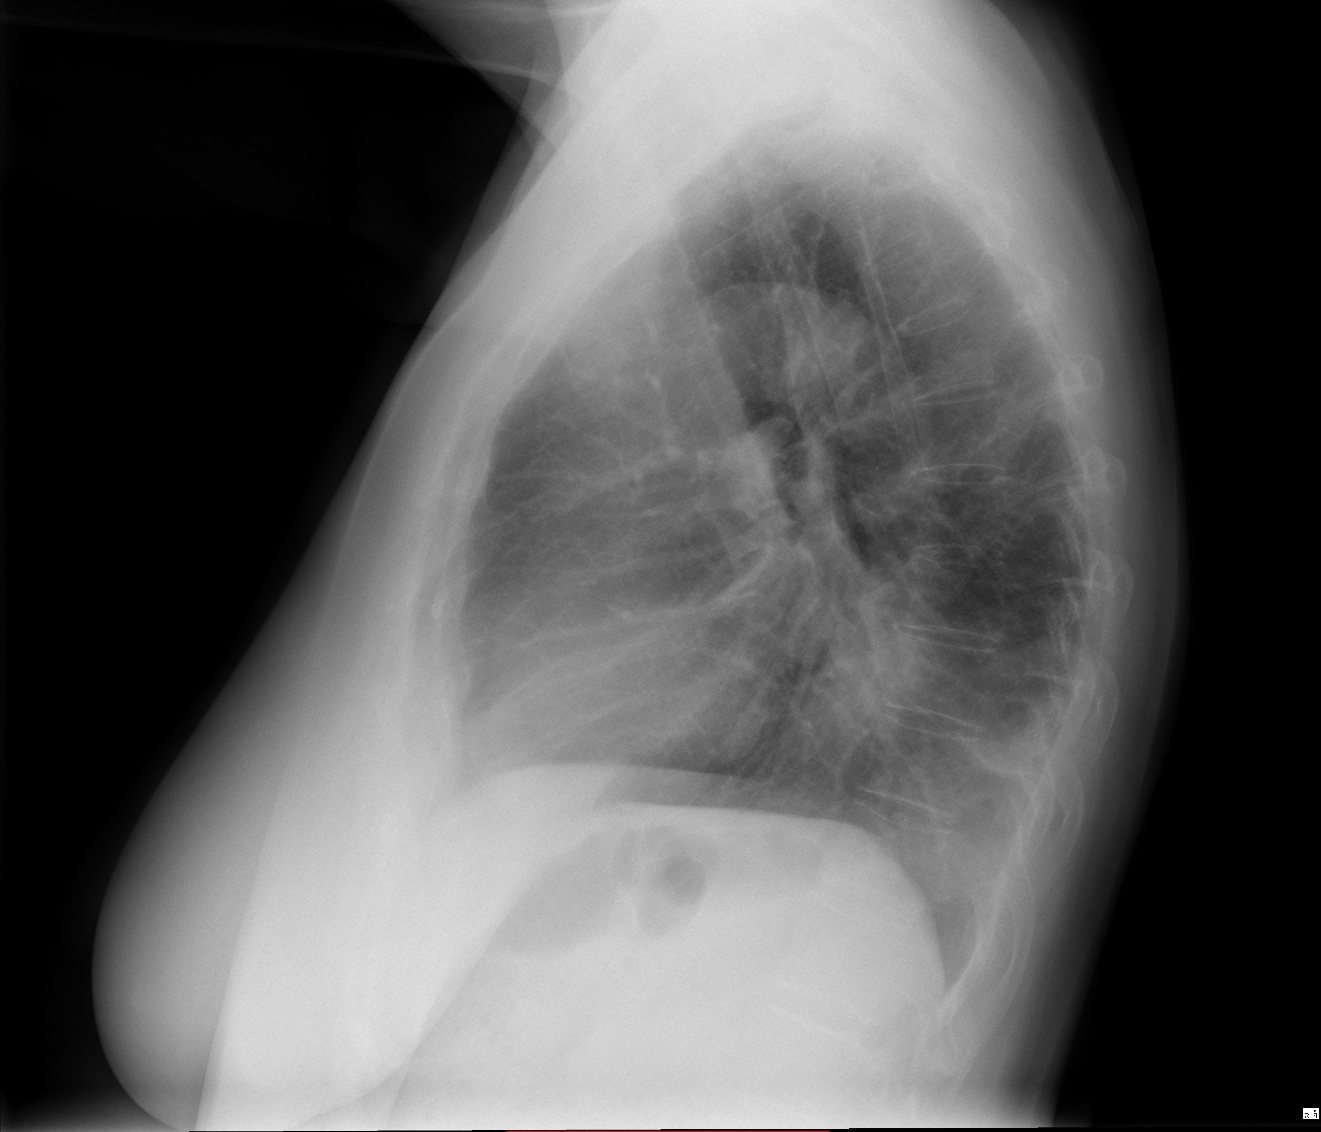

CASO: Febrícula y tos de 4 días de evolución.

Hallazgos:

- En la placa PA se observa una asimetría en los hilios pulmonares, el hilio izquierdo tiene una densidad aumentada.

- Tras examinar la placa lateral se observa un aumento de densidad en la columna que puede ser compatible con una condensación, es el signo de la desnificación vertebral.

SIGNO DE LA DENSIFICACIÓN VERTEBRAL: En la radiografía lateral normal, la densidad de la columna torácica tiende a disminuir desde la parte superior hasta el diafragma; la alteración de ese patrón por la presencia de una densidad superpuesta a la columna, indica la existencia de una consolidación pulmonar. Este signo adquiere especial valor cuando en la proyección posteroanterior la consolidación está oculta en el espacio retrocardíaco o en la base pulmonar.